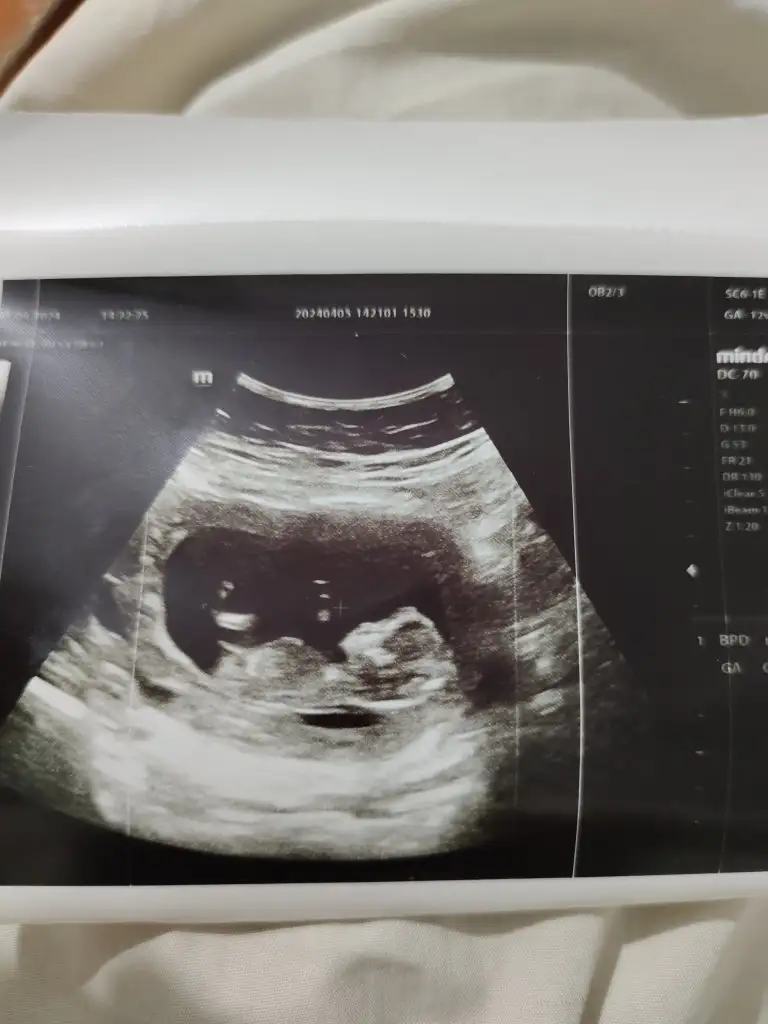

Kızlar çok şükür bebeğim iyi herşey yolunda cinsiyetini kıza benziyor bir ay sonra kesinleşir dedi sizce ne bakar mısınız 😇12+2 bugün

Eklentiler

• IMG_20240405_161406.webp

IMG_20240405_161406.webp

27 KB · Görüntüleme: 83

• IMG_20240405_161353.webp

IMG_20240405_161353.webp

28,1 KB · Görüntüleme: 88